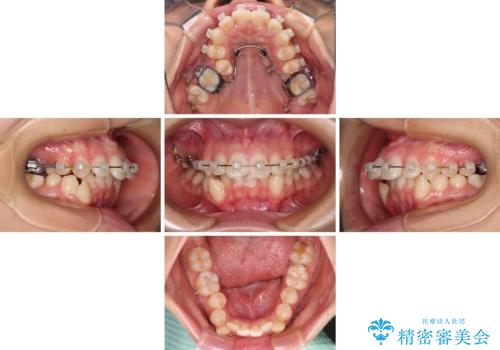

- 咬み合わせと、前歯のデコボコや八重歯、飛び出した口元を気にして来院された患者様です。

上顎は歯列不正が強く、右側臼歯部の咬み合わせは歯1本分ずれている状態でした。

補助装置を用いて奥歯の咬み合わせを改善しながら歯列を後方に移動させ、上下左右第一小臼歯を4本抜歯することで八重歯や口元の突出感を改善することとしました。

奥歯の咬み合わせの不正が顕著であったため、表側のワイヤー装置を選択して矯正治療を行うこととしました。

補助装置を併用したおかげでスムーズに奥歯の咬み合わせを改善することができ、我々も予想できないくらい理想的な仕上がりにすることができました。